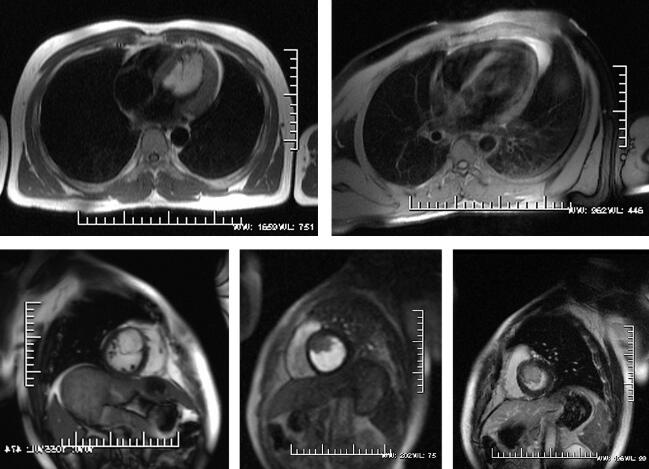

磁共振成像检查:应用1.5T场强的MRI仪(Magnetom Sonata,Siemens),患者取仰卧位,头先进,32通道心脏表面线圈,心电门控,采用黑血序列进行横断位平扫,然后行四腔心、两腔心长横断位及两腔心短横断位电影序列扫描。静息灌注序列采用两腔心短横断位及四腔心平面,采用钆喷酸葡胺对比剂,按0.2mmol/kg体重注射。灌注对比剂流率为5ml/s,总量8ml。延迟增强扫描于首次心肌灌注后立即以2ml/s的流率注射总量14ml的对比剂,于8~10分钟进行延迟扫描。心脏MRI检查方案见表1。影像学检查见图1。

MRI表现:心内结构未见明显异常,各房室未见明显增大;HASTE见左室内占位,与室间隔相连,为均匀高信号,压脂后信号减低;心脏电影显示各节段运动正常,各瓣膜收缩舒张未见明显异常,未见返流信号;心肌静息灌注显像见左室内充盈缺损,心肌未见明显异常灌注,心肌延迟强化序列显示心肌内未见明显异常强化灶,病灶未见明显强化。

图1 心脏脂肪瘤

心脏脂肪瘤是仅次于心脏黏液瘤的常见心脏良性肿瘤,可以发生在心脏任何部位,如果起源于房间隔或室间隔,可引起心律异常,在瓣膜口附近可引起心腔梗阻。

心脏脂肪组织的MRI表现特殊,无论T1WI还是T2WI上均呈均匀高信号,边界清楚,在脂肪抑制图像上信号强度降低,增强扫描无强化。